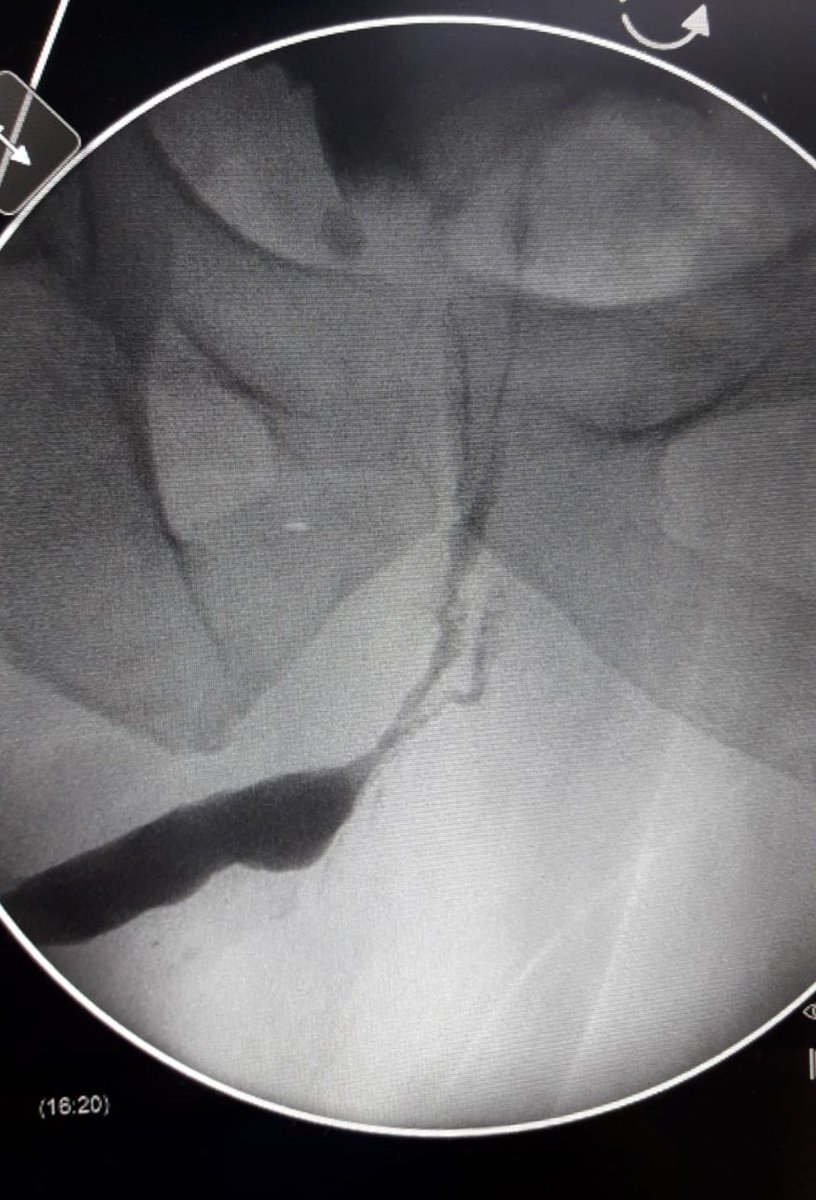

The lithotripsy and Endourology Unit of La Fe University and polytechnic Hospital renews the ISO 9001:2015 and UNE 179003:2013 certification for the Health services it provides. Proud of my Team!!!! @InfoAeu @EndoLapRobAEU @HospitalLaFe @eulis_uroweb